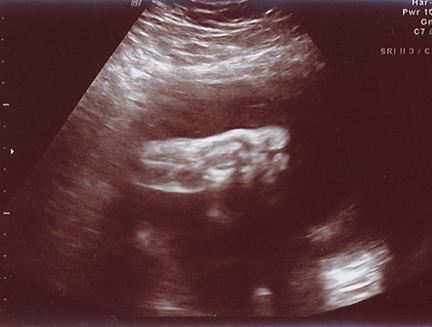

December 10, 2005 - Mandy has gone in for her doctor's appointments, and Evan is doing very well! He is a little over 2 pounds, and he is at 29 to 30 weeks! He is a very active little fellow, Manders can definately tell you that! We plan to go to Sioux Falls at least twice a week when Mandy is at 32 wks. She will undergo NoStress tests. Mandy has a lot better details for you than I would! She always keeps up with Evan on her LiveJournal site!